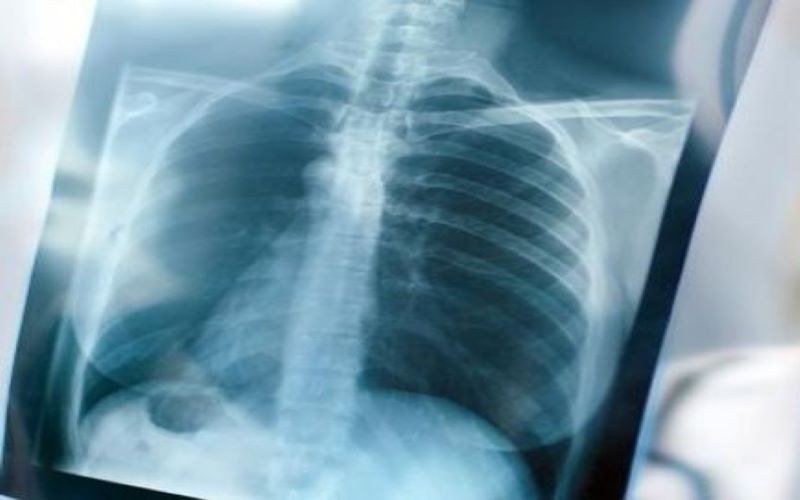

التهاب الرئة الشديد.. 7 أعراض تحذيرية لا تهملها

التهاب الرئة الشديد.. 7 أعراض تحذيرية

نيسان ـ مع اجتياح فيروس كورونا العالم، تضاعفت معدلات الإصابة بالتهاب الرئة الشديد بين مختلف الفئات العمرية، فما أبرز أعراضه التحذيرية؟

وفقا لموقع lung العالمي، فإن التهاب الرئة عبارة عن حالة أو عدوى تحدث عندما يكون هناك التهاب الأكياس الهوائية الدقيقة في رئتيك (الحويصلات الهوائية).